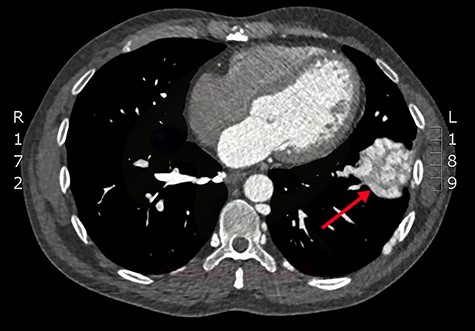

Axial slice from the CTPA, demonstrating the large, complex PAVM in the left lung’s lower lobe (red arrow).

Concerned for pulmonary embolism (PE), a computed tomography pulmonary angiogram (CTPA) was arranged. PE was excluded; however, it did reveal a complex left-sided intra- and extrathoracic vascular malformation within the anteromedial segment of the left lung’s lower lobe, the lingula segment, the subdiaphragmatic space and the left chest-wall (Figs. 1 and 2). The arterial supply derived from large tortuous vessels arising from a combination of the coeliac trunk, six posterior intercostal arteries and the left inferior phrenic artery (Fig. 3). It then communicated with the left upper and lower lobe subsegmental pulmonary arteries, and the left lower lobe pulmonary vein. Subsequent echocardiography was normal, with no significant valvular pathology—evidencing that the pansystolic murmur was an arteriovenous bruit.